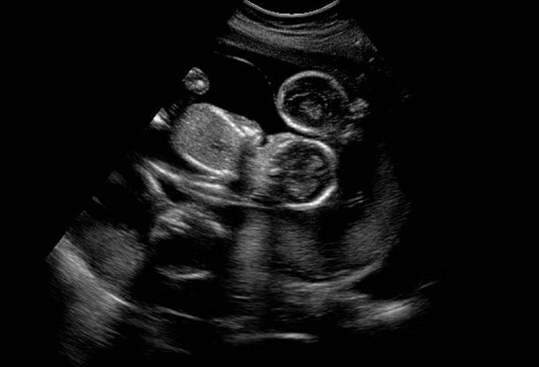

真实怀孕时,血HCG值会呈现规律性上升,通常每48小时翻倍增长。而假性怀孕的激素波动缺乏规律性,验孕棒可能呈现弱阳性或时隐时现的假阳性。专业妇科检查会发现,假孕者的子宫大小与停经月份不符,B超检查始终无法探测到孕囊结构。